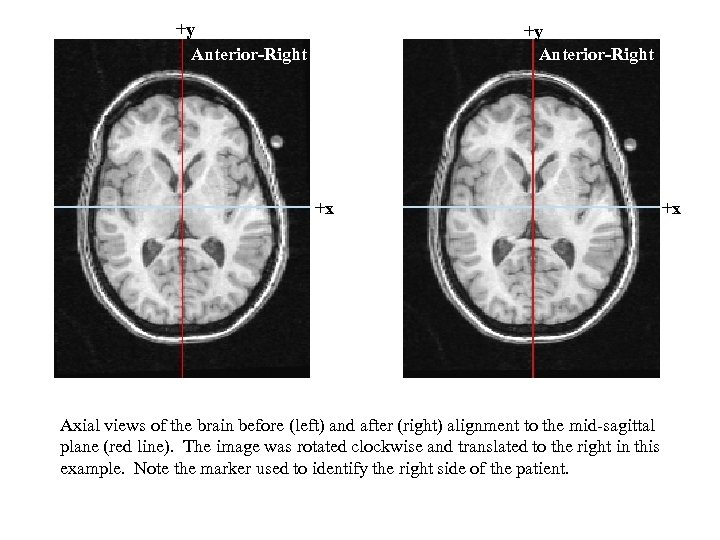

+y Anterior-Right +x Axial views of the brain before (left) and after (right) alignment to the mid-sagittal plane (red line). The image was rotated clockwise and translated to the right in this example. Note the marker used to identify the right side of the patient. +x